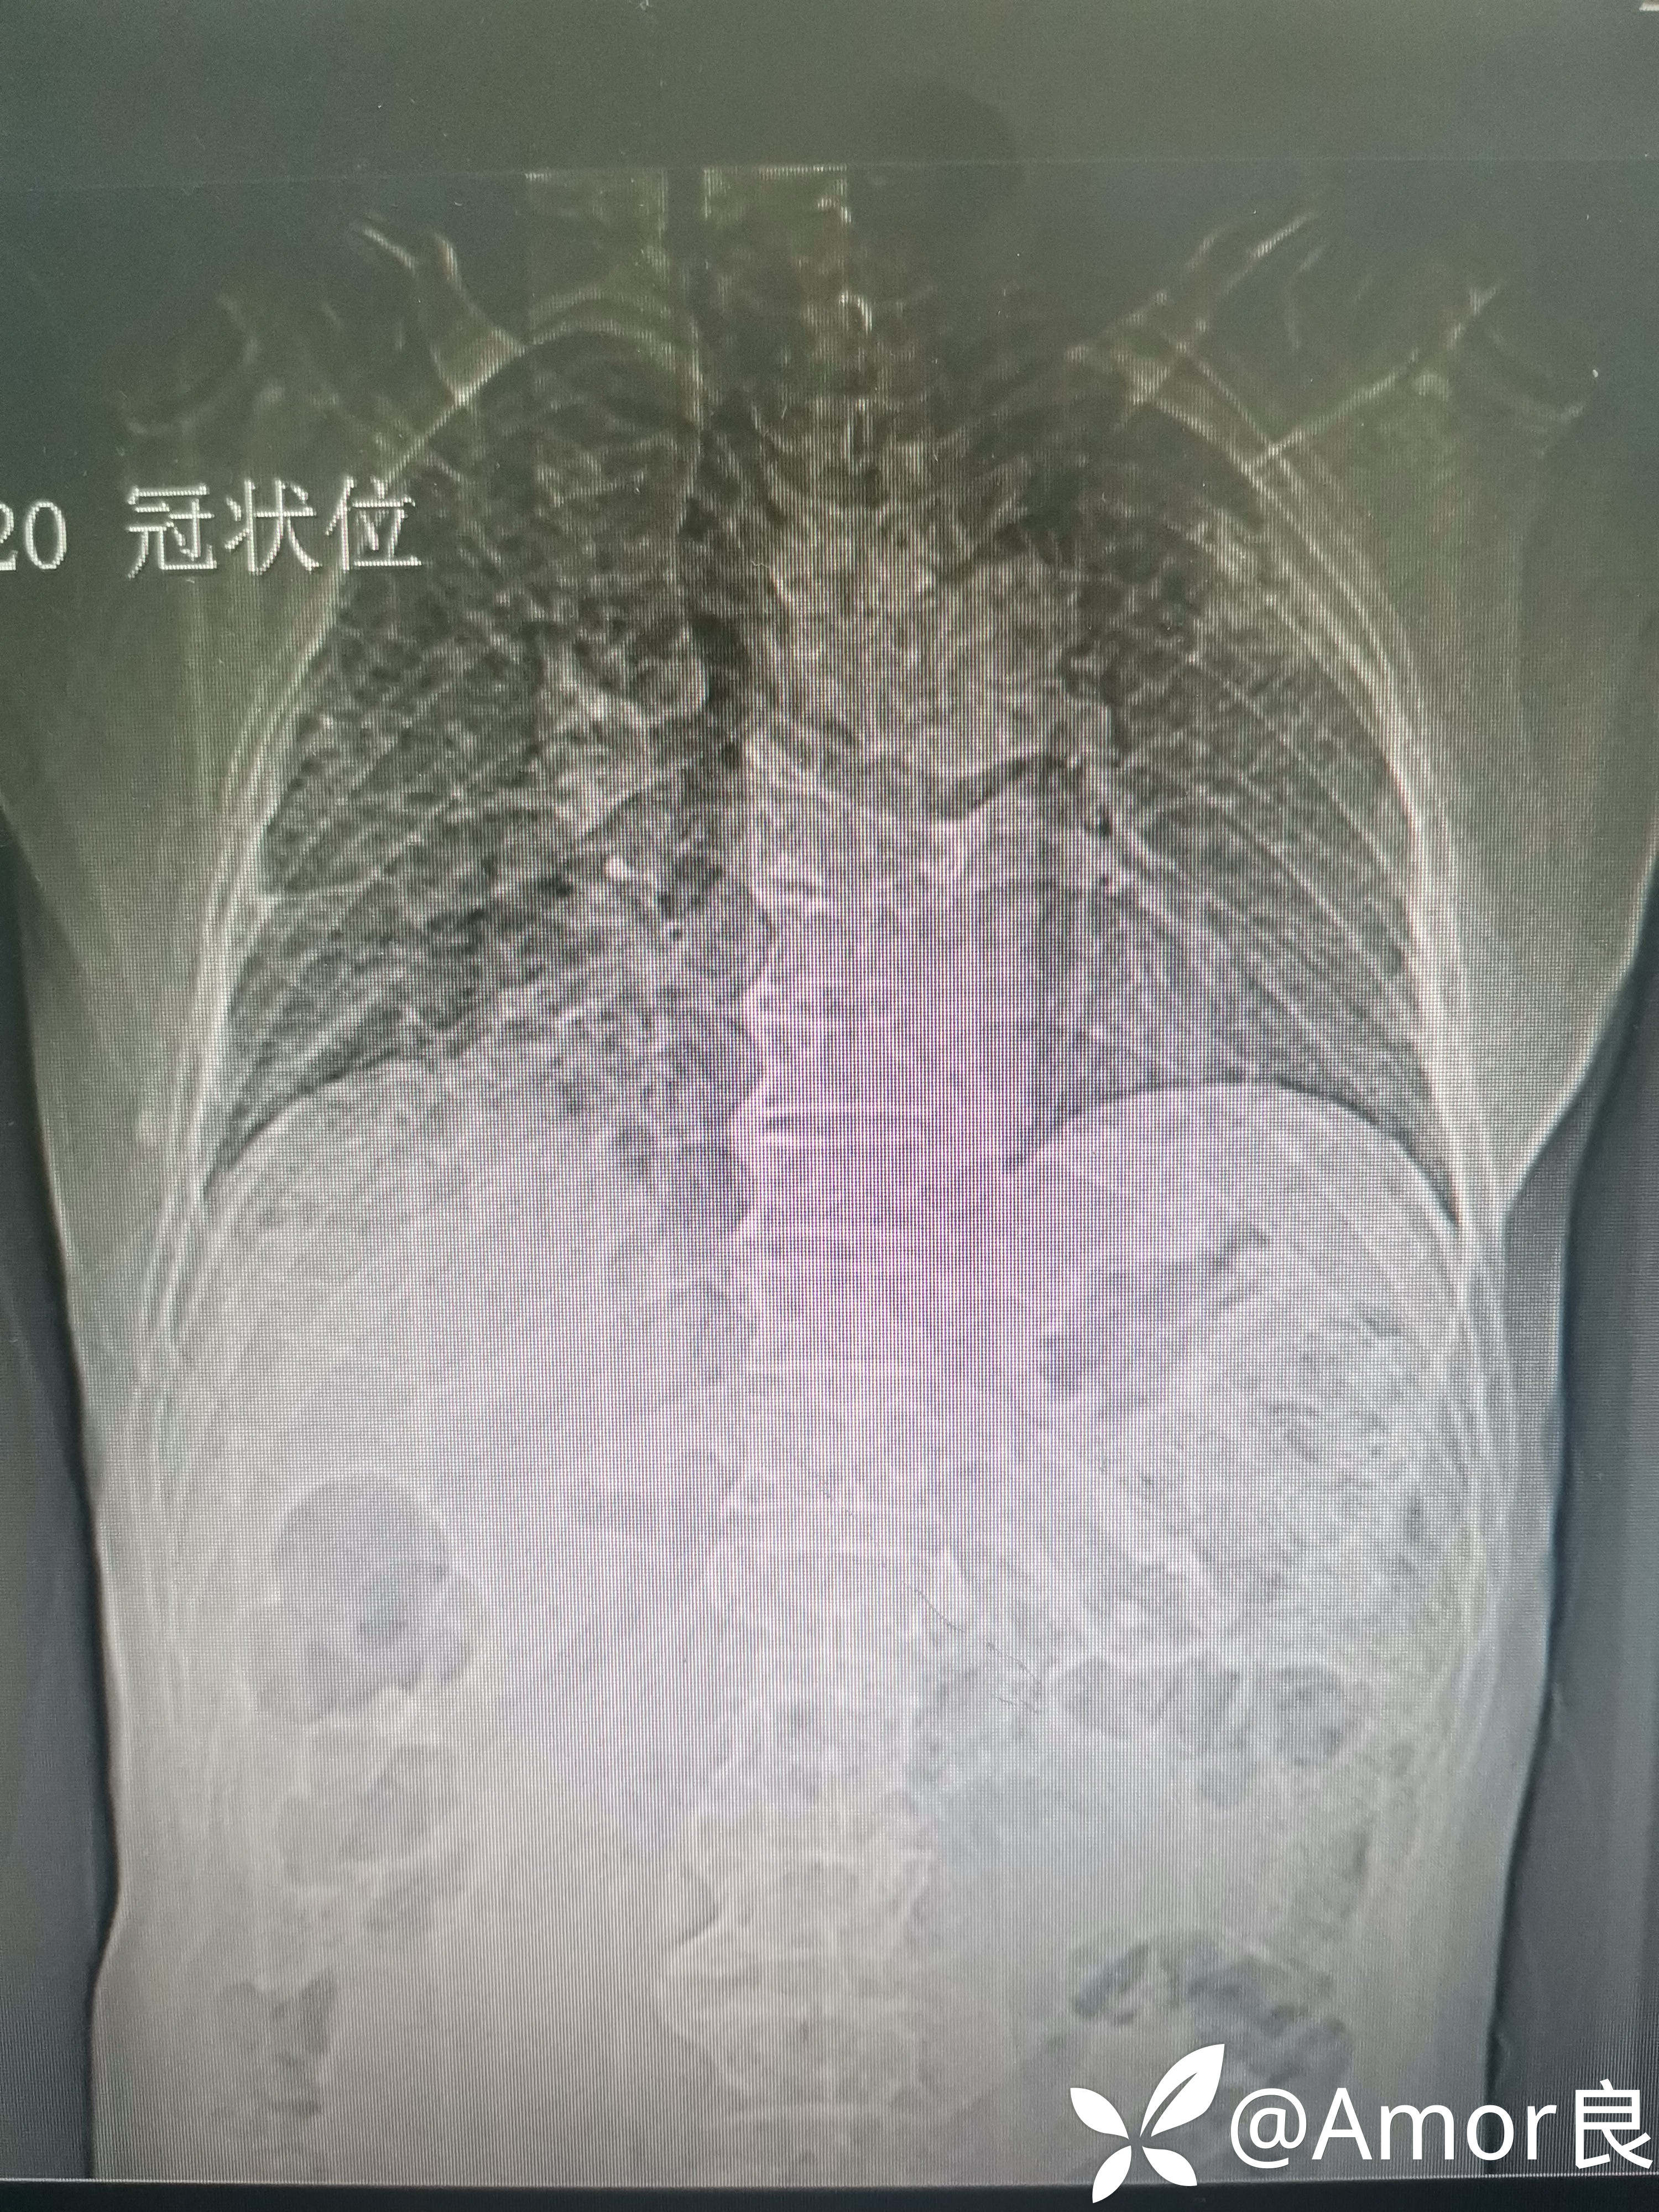

胸片如下:

胸部CT如下: